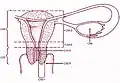

Útero e tubas uterinas

Útero e tubas uterinas -

Esquema do útero e ovário

Esquema do útero e ovário -